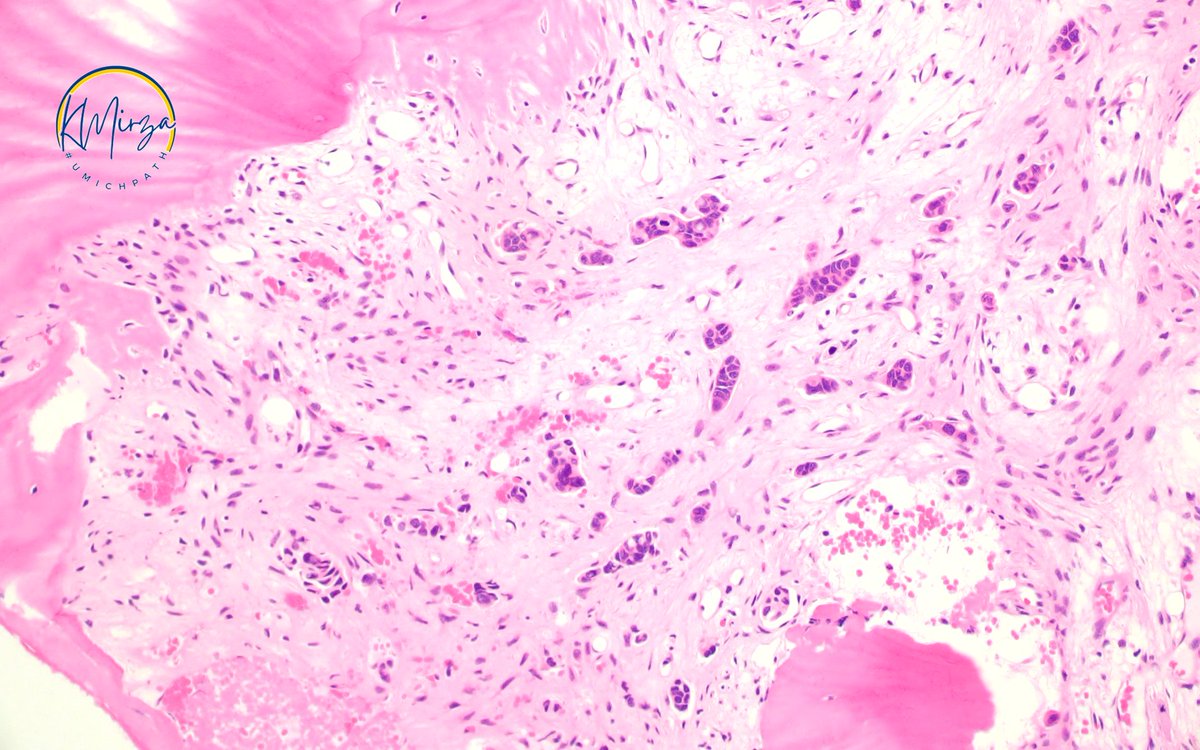

#Pathresidents: Let’s take a look at two biopsy cores (from the same patient) and decide what to call them.

Take a look at both cases (“A” in this post, “B” in reply). Cast your vote. Then, read on for some teaching points geared towards trainees and general fans of #GUPath.